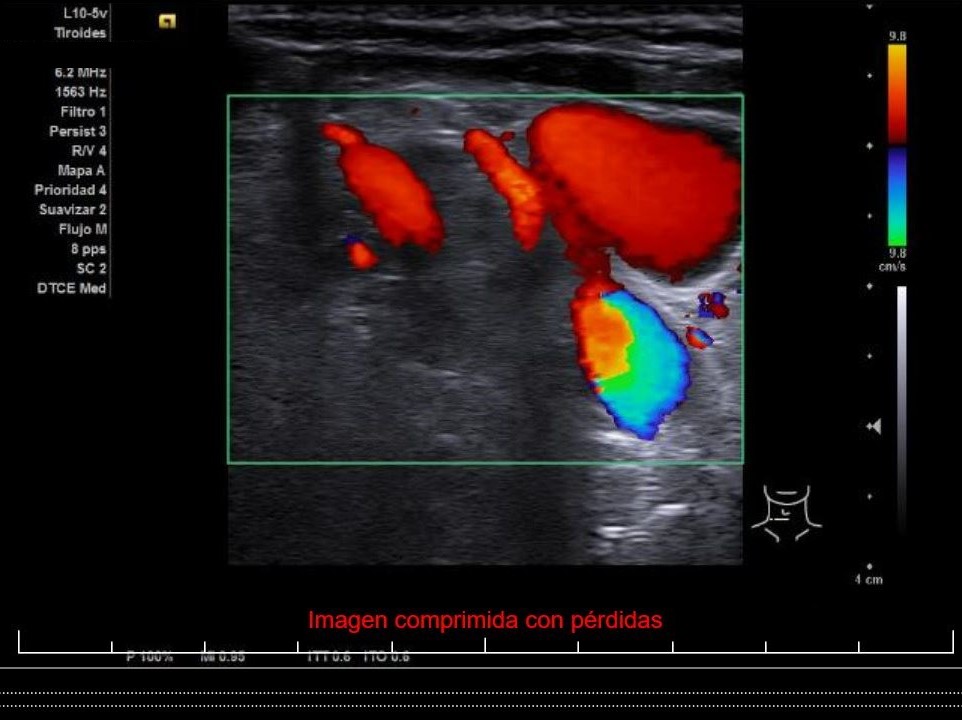

Descripción de los hallazgos ecográficos y las imágenes más relevantes para la resolución del caso

Se aprecia un tiroides de características ecográficas compatibles con tiroiditis, sin cambios respecto a ecografía previa, al igual que la grasa peritiroidea derecha, pero de manera incidental se observa un aumento del calibre fusiforme de la yugular externa derecha con respecto a la izquierda, con flujo vascular reducido.

Ante la sospecha clínica y ecográfica de trombosis o flebectasia yugular se derivó a la paciente a urgencias, donde se realizó una ecografía reglada informada como normal, además de Eco-Doppler de troncos supraórticos también informada como normal.

Flebectasia yugular derecha.